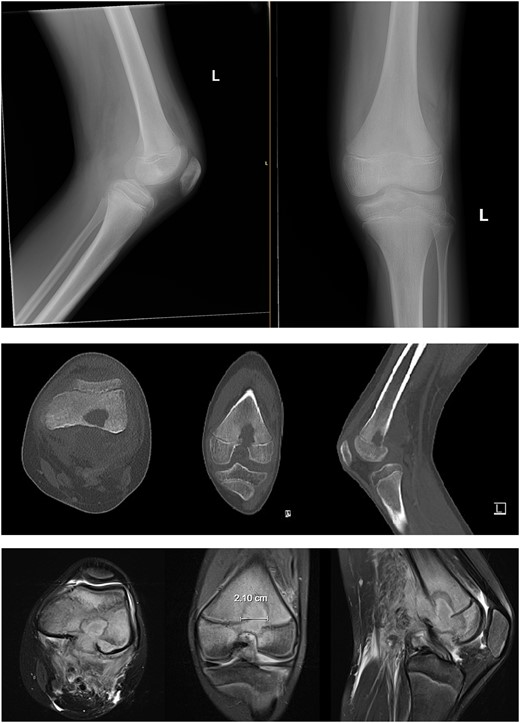

An 11-year-old healthy male presented with posterior left knee pain, which began 4 days after twisting his knee at a trampoline park. The pain progressed to a point where he was unable to bear weight on his left leg, and the knee became locked in flexion due to muscle spasms and pain. After three visits to outside facilities over 2 weeks, the patient finally received an orthopedic consultation. While radiographs were unremarkable, magnetic resonance imaging (MRI) revealed a large fluid collection posterior to the distal femur, suggestive of osteomyelitis, and Brodie’s abscess and associated local destruction of the posterior femoral cortex (Fig. 1a and c). The patient was then transferred to our institution for definitive management. Upon presentation, the patient was febrile (39°C) and nauseous with one episode of emesis. Physical examination revealed a tender and warmer left knee without open wounds. The patient denied a knowledge of current dental carries or a history of recent dental procedures and denied recent history of a streptococcal infection. Laboratory tests showed leukocytosis of 14 600 μl of white blood cells (WBC), elevated C-reactive protein (CRP) of 18 μg/ml (normal <0.3 μg/ml), and an elevated erythrocyte sedimentation rate (ESR) of 18 mm/h (normal <15 mm/h). A CT scan at our institution recapitulated findings suggestive of osteomyelitis, cortical destruction, and a noted thrombophlebitis of the popliteal vein (Fig. 1b).

Preoperative radiography, CT, and MRI. The radiographs were read as normal by the radiology, while the CT and MRI were read osteomyelitis with Brodie’s abscess involving the distal femoral epimetaphysis with destruction of the posterior cortex and associated 7 cm popliteal fossa abscess, along with a suspected nonocclusive septic thrombophlebitis of the popliteal vein mentioned in the report on the CT.